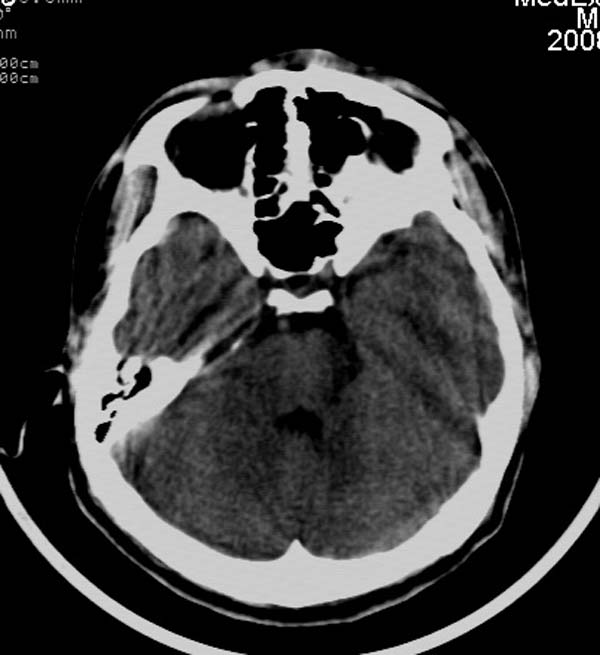

患者,男,24岁。头面部外伤后意识障碍1小时。

小脑幕缘密度增高,考虑有少量出血,建议复查

考虑右侧天幕缘少量蛛网膜下腔出血;建议:必要时复查。

1)考虑少量蛛网膜下腔出血;建议:必要时复查。2)桥前池及左侧环池表皮样囊肿可能。建议:行mri检查。

考虑右侧天幕缘区域少量蛛网膜下腔出血。

当ct表现不明显,临床症状相当明显时,建议mri+dwi序列除外弥漫性轴索损伤之可能。

一侧密度增高,是否考虑为硬膜下血肿,前额血肿真好对冲伤,桥小脑脚增宽建议进一步检查